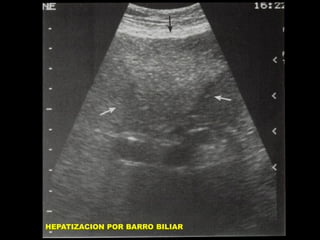

INSUFICIENCIA HEPATICA

HEPATIZACION VESICULAR

HEPATIZACION POR BARRO BILIAR